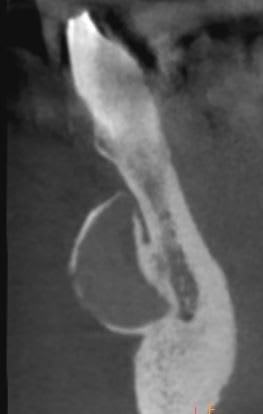

J'ai vu ce patient en urgence pour abcès 26, je n'ai rien remarqué cliniquement, mais j'ai fait une 3D, et je suis tombé là dessu, je vais adresser rapidement, mais auriez vous une idée?

Sans être un as de la patho, j'aurais tendance à penser que les contours sont nets, ça ne semble pas envahissant, c'est asymptomatique, ça fait bien lésion kystique quelconque.

J'ai du mal à lire les 3D quand je ne peux pas les faire défiler moi même, mais la lésion semble bien en rapport avec un des apex, dans la zone où la corticale est perforée. Tests de vitalité? Et puis bêtement, si tu mets un coup de sonde dedans, il se passe quoi?

Tiens, d'ailleurs, en re regardant la deuxième et troisième ligne de coupe, c'est quoi la merdouille en vestibulaire des apex, au niveau de la corticale? Un odontome ou équivalent?

Aucune lésion apicale, et pas d'odontome.Je vais adresser, je vous tiendrai au courant

il a pas eu une prothèse au menton ?

Et oui c'était bien ça...Il ne me l'avait pas dit.

Il ne sait pas en quoi elle est

Tu t'occupes de son cas, il a une radio 3D et il ne mentionne meme pas son silicone esthétique du menton....! Doit etre sacrément complexé par son menton fuyant.

Ben non même pas curieusement, mais il a ça depuis 40 ans il a zappé en fait.

Ouaip, fred, donc il etait dans ses vertes années , c'etait bien de la chirurgie esthétique ou un global LEFORT II?

Oui tout à fait faite par un chir maxillo-facial qui lui a refait le nez aussi